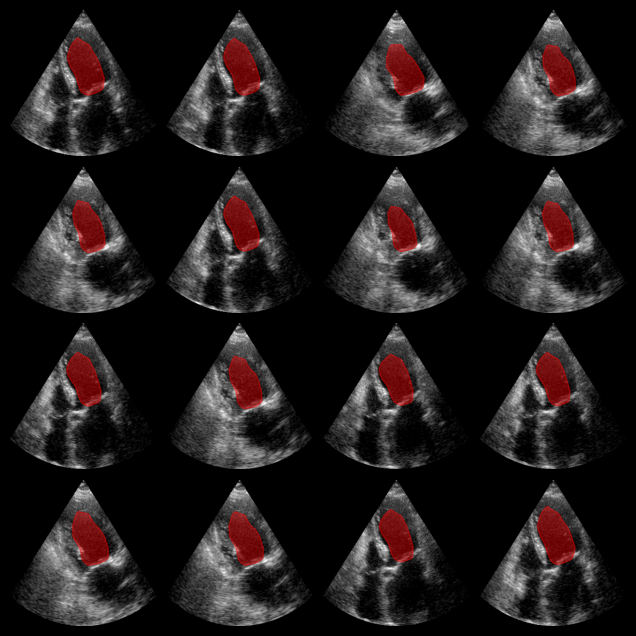

EchoNetDynamic segmentation results:

The red overlay shows the predicted left ventricle mask for each image.

EchoNet-Dynamic Example Output

Now we proceed with the second segmentation model, EchoNetDynamic model, which expects RGB input images. The model was trained on the EchoNet-Dynamic dataset, but here we apply it to CAMUS data for demonstration.

for ax, mask in zip(axes, masks_echonet):

plot_shape_from_mask(ax, mask, color="red", alpha=0.4)